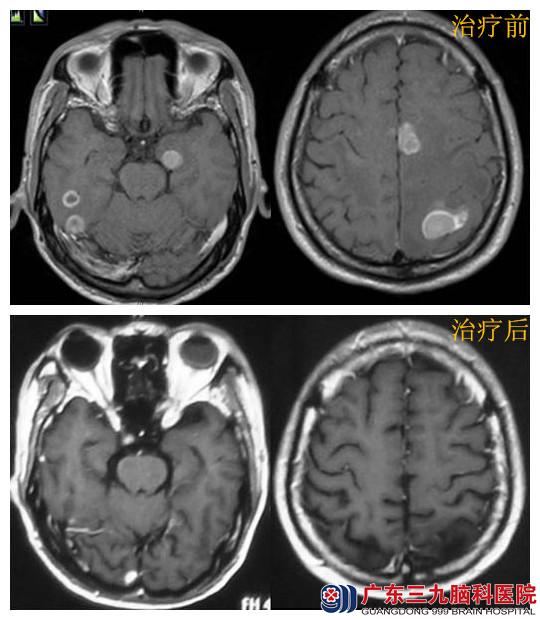

【肺癌脑转移瘤案例分析】

范某某,男,58岁,因左上肢麻木20天,右下肢乏力伴头晕、头痛15天,于2014年8月中旬入广东三九脑科医院肿瘤综合治疗中心就诊。

入院行胸部CT示右肺中央型肺癌可能可能性大,行肺部肿物支纤镜活检病理示:右肺中叶低分化腺癌。头颅MRI诊断:颅内多发占位性病变,病灶达12个之多,大小不等,最大的直径近3cm,这种情况已无手术机会,常规的全脑放疗不能照射足够的剂量,不能很好的消灭肿瘤,因此必须使用诺华刀。8月23日行头颅多发病灶x刀治疗,确定10个病灶,10个等中心,8月27日-10月10行肺部适形调强放疗,完成剂量60GGy/30f,放疗期间同步顺铂化疗,9月6日开始行全脑放疗,完成剂量36Gy/18f。诺华刀后3月复查头颅MR示肿瘤完全消失,患者恢复正常工作。